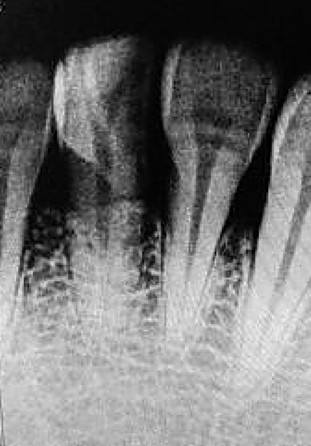

周女士按医生要求给牙齿拍了片。几个小时过去,医生综合检查情况给出了意见:第一,患者的牙齿总体健康,未见明显虫牙;第二,牙齿的牢固度良好,牙根较深;第三,牙齿受伤后留下的并非斜裂伤,而是横断面伤。诊断结果定性为:牙根中部折断。